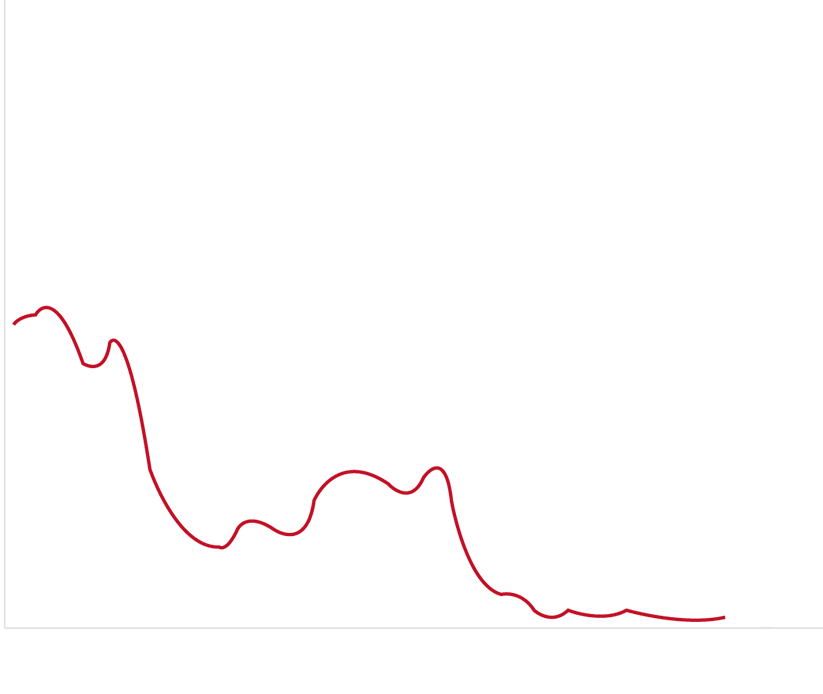

是一种基于血红蛋白对不同波长光吸收系数不同的原理而设计的智能染色成像系统,兼有电子染色和光学染色功能,能够凸显粘膜血管结构,有助于病灶部位识别和诊断,为临床医生术中判断提供参考信息。

血管对比度分布光谱曲线

VIST光谱